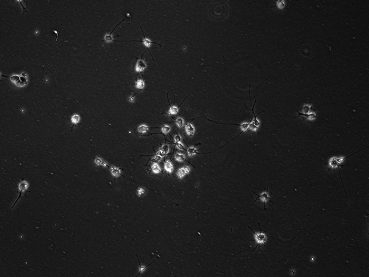

Patient-derived pediatric PFA ependymoma cell lines grown under hypoxic conditions display distinct morphologies (10X).

Patient-derived paediatric PFA ependymoma cell lines grown under hypoxic conditions display distinct morphologies (10X).